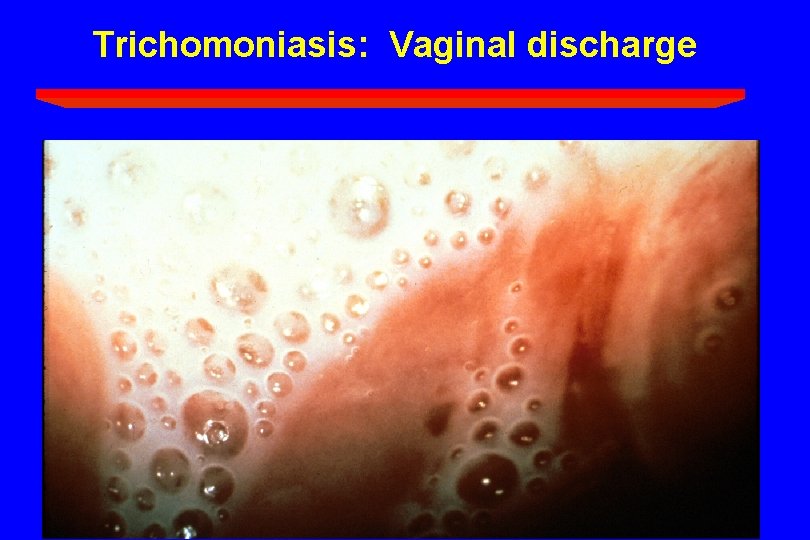

Trichomoniasis: Vaginal discharge